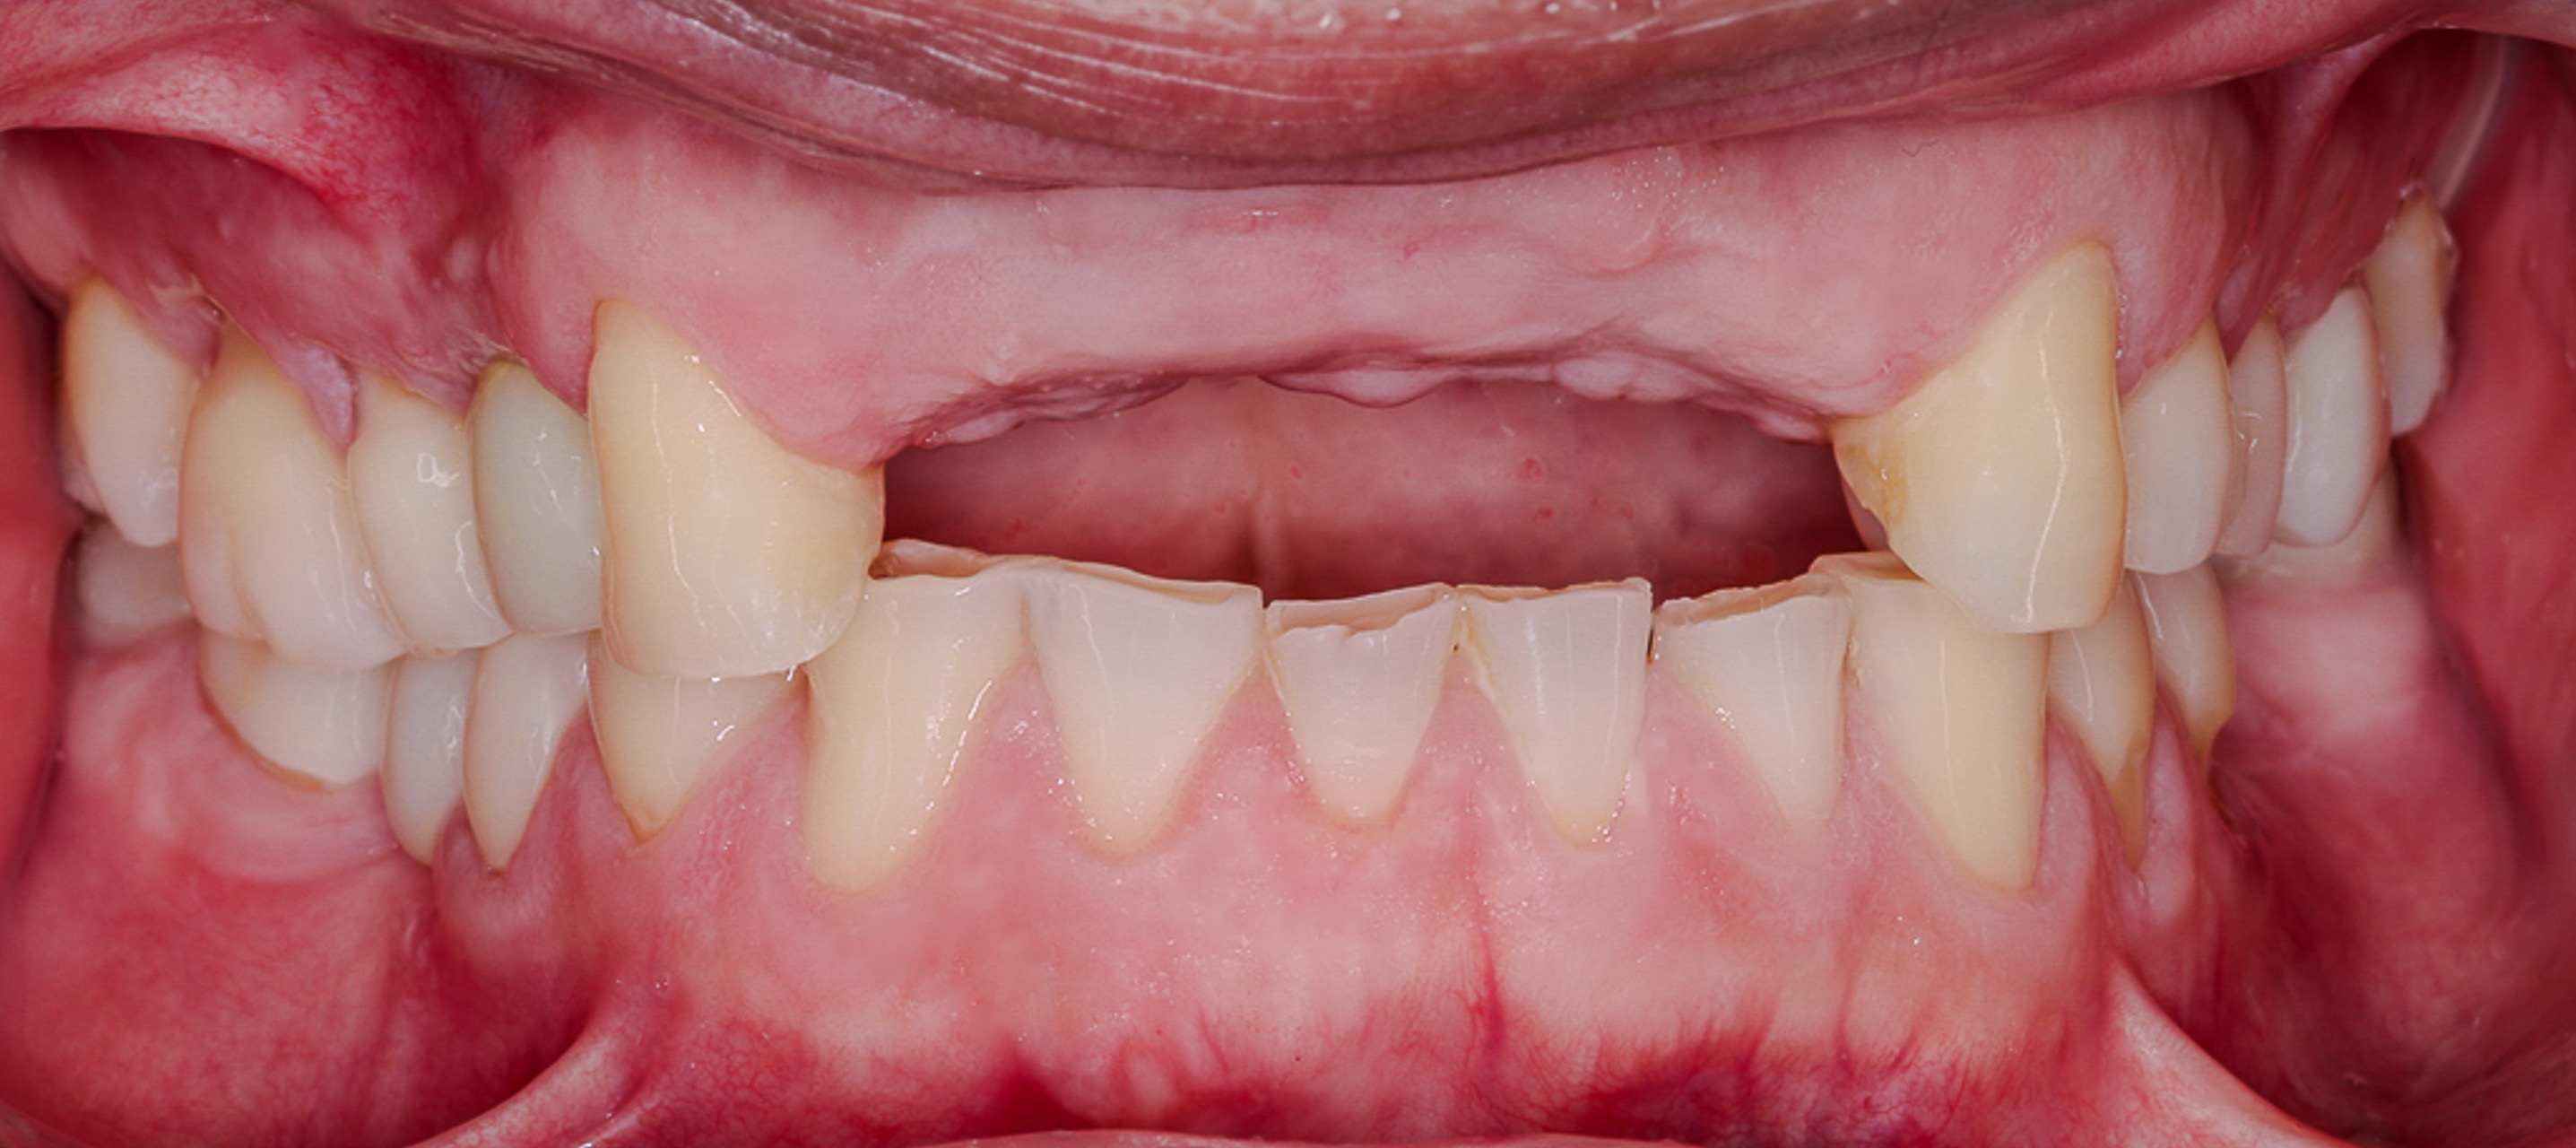

Ivan presented with unrestorable maxillary front teeth (#7–10) due to a combination of subcrestal fractures and caries. The compromised teeth were affecting both function and esthetics, with structural damage extending below the bone crest.

September 25, 2021Initial evaluation and documentation of failing maxillary front teeth with subcrestal fractures and caries involving teeth #7–10.

Ivan’s maxillary anterior region was restored from failing, unrestorable teeth to a stable, implant-supported reconstruction. The guided bone regeneration created sufficient bone volume for ideal implant placement, and soft tissue management allowed for a natural, harmonious smile line.

Function, phonetics, and esthetics were significantly improved, and the final restorations blend seamlessly with Ivan’s facial features. This case demonstrates how a biological, staged approach to extraction, GBR, and implant placement can successfully rebuild the anterior maxilla after significant structural compromise.